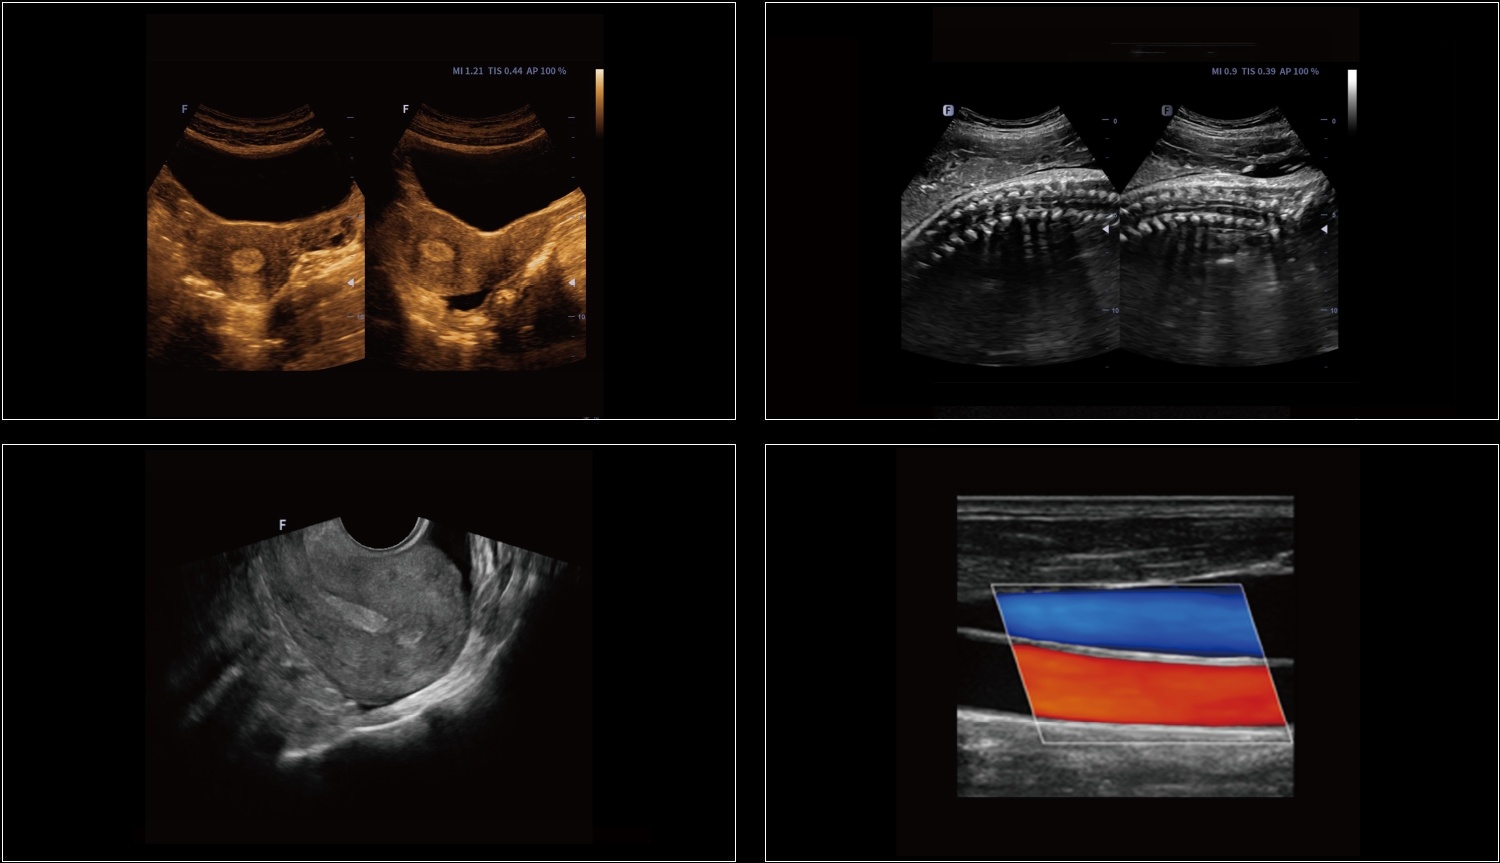

Rozszerzone pole widzenia wyświetla więcej informacji obrazowych bez utraty jakości obrazu. Jest wygodnym podejściem do dużych organów, zwłaszcza struktur układu mięśniowo-szkieletowego. Posiada wskazania dotyczące kierunku i prędkości skanowania.

Elastografia w czasie rzeczywistym to nowa nieinwazyjna i bezbolesna technika, która pomaga określić twardość organów oraz innych struktur takich jak piersi czy tarczyca. Obrazowanie elastyczne dostarcza użytkownikom dynamicznych informacji wizualnych i pokazuje sztywność organów, co jest pomocne w bezpośredniej i ilościowej diagnozie oraz leczeniu.